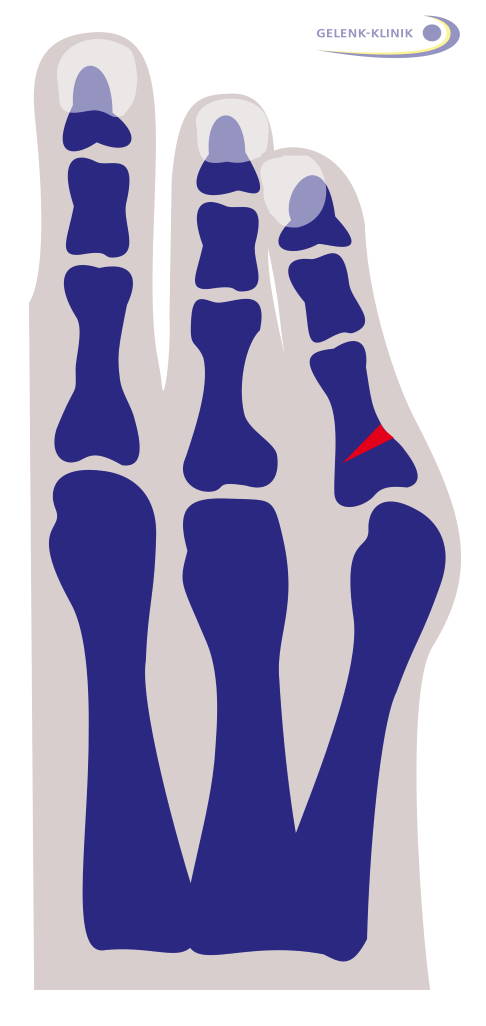

Der Schneiderballen (Digitus quintus varus) ist eine Fehlstellung des kleinen Zehs, bei der es zu Reizungen an der Außenkante des Fußes kommt. Man bezeichnet ihn in der Medizin auch als Bunionette. Dabei handelt es sich um einen Schiefstand des kleinen Zehs, ganz ähnlich wie bei der Hallux valgus-Fehlstellung der Großzehe.

Beim Schneiderballen ist der kleine Zeh in seinem Grundgelenk nach innen gerichtet und kann die benachbarten Zehen überlagern. Im Bereich dieser Fehlstellung entsteht häufig eine Gelenkarthrose oder eine schmerzhafte Schleimbeutelentzündung (Bursitis). Auch Schwielen und Hornhaut an der betroffenen Stelle werden häufig beobachtet.

Die häufigste Methode ist die sogenannte Chevron-Osteotomie. Hierbei erfolgt eine v-förmige Knochendurchtrennung an der Außenseite des fünften Mittelfußknochens. Der Mittelfußkopf wird nach der Knochenabtragung nach innen verschoben und mit einem Draht oder einer Schraube befestigt. Der verbleibende Knochenüberstand wird abgetragen. Diese Maßnahme korrigiert die Fehlstellung der Kleinzehe (Digitus quintus varus) und verschmälert den Vorfuß.